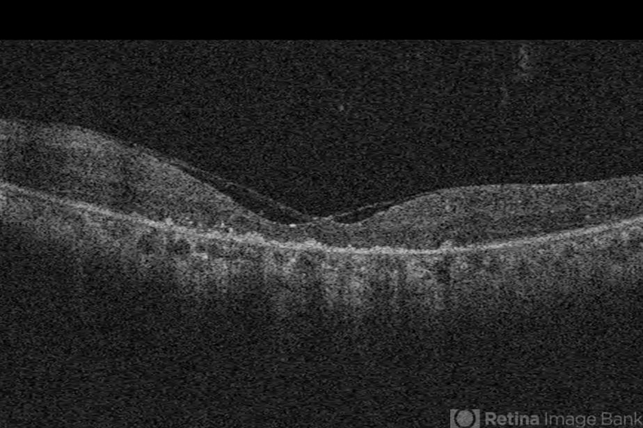

Optical coherence tomography system

Cirrus - Description

- Ushers 2.